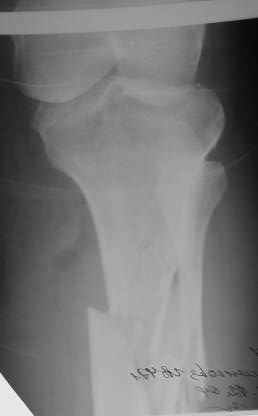

Больная поступила 11 12 2004 с открытым оскольчатым переломом в/3 обеих костей правой голени со смещением после автодорожной аварии. (1Б по Каплану, тип 2-классификация Gustilo-Anderson).

Наложено скелетное вытяжение . обработана рана, наложены швы, заживление идет благоприятно. На контрольных рентгенограммах стояние отломков несколько улучшилось. Рис 1,2 Обдумываем в коллективе несколько вариантов возможного лечения:

Рентгенограмма при поступлении. Думаю на ней видно распространение линии перелома вниз